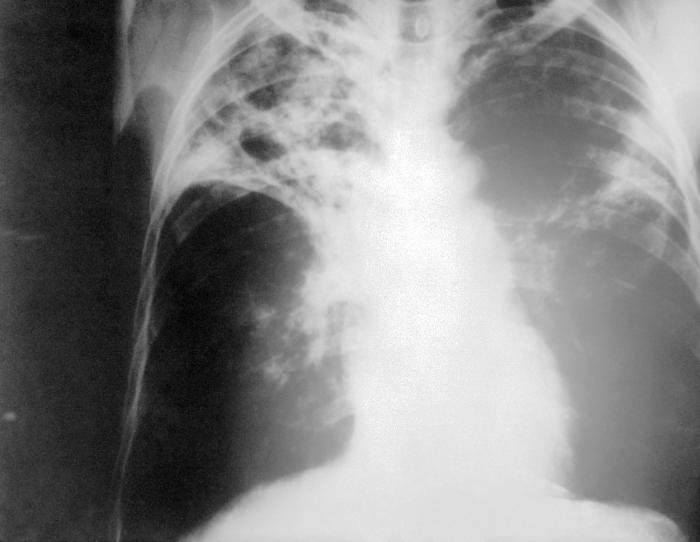

At some point the centers of the tubercules may liquify, which produces a very conducive enviornment for the bacteria and rapid spread of the disease.  Only a very small precentage of infected individuals will progress to this stage (Todar 2005).  The following picture is an example of what cavity formation looks like in the lungs.

X-Ray image of patient's lungs with M. tuberculosis infection from CDC website